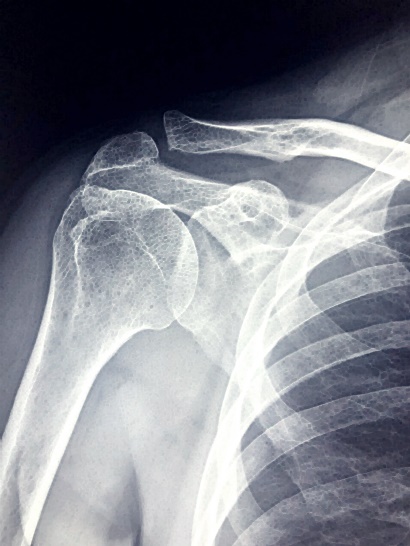

어깨는 우리 몸에서 가장 움직임이 많은 관절 중 하나입니다. 이로 인해, 어깨 통증은 일상생활에 큰 불편을 초래할 수 있으며, 다양한 원인으로 인해 발생할 수 있습니다. 오늘 포스팅에서는 어깨통증의 주요 원인에 대해 알아보고 그로 인해 증상은 어떤 것들이 있는지 같이 알아보도록 하겠습니다.

어깨통증의 주요 원인

✅ 어깨 관절염

시간이 지남에 따라 어깨 관절의 연골이 마모되어 통증을 유발할 수 있습니다. 이는 주로 노화 과정에서 나타납니다.

1. 노화: 가장 일반적인 원인으로, 나이가 들면서 관절 연골이 자연스럽게 마모됩니다.

2. 외상 후 관절염: 어깨 부상이나 골절 후에 발생할 수 있으며, 과거의 부상이 관절염으로 이어질 수 있습니다.

✅ 어깨 탈구 또는 부분 탈구

어깨 탈구는 어깨 관절이 구성하는 뼈들이 정상적인 위치에서 벗어나는 상태를 말합니다. 부분 탈구는 뼈가 부분적으로만 벗어난 상태로, 전체 탈구보다는 덜 심각하지만, 적절한 치료를 받지 않을 경우 장기적인 문제를 유발할 수 있습니다. 어깨 탈구와 부분 탈구는 강한 충격이나 부상으로 인해 발생할 수 있으며, 심한 통증과 함께 어깨의 움직임을 제한합니다.